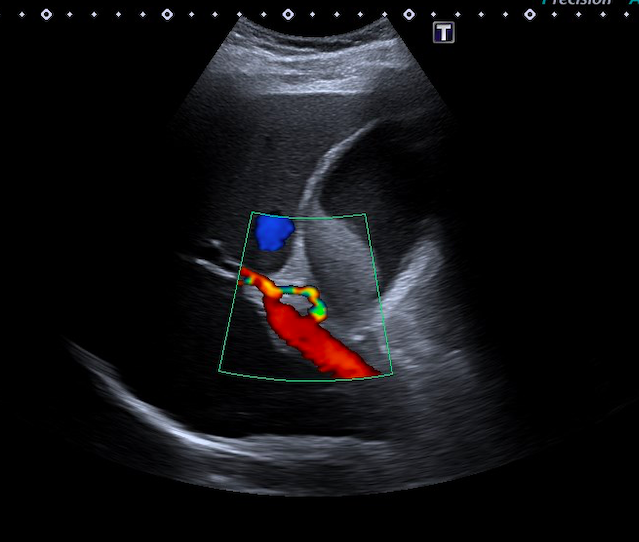

Se realiza una exploración abdominal, donde se objetiva distensión de la vesícula biliar, con un diámetro longitudinal de 10 cm, y engrosamiento de la pared de 4 mm (figura 1), abundante barro biliar (figura 2) y la presencia de una litiasis en cuello vesicular (figura 3). Murphy ecográfico positivo. Doppler negativo, sin dilatación de la vía biliar (figura 4). No líquido perivesicular. Resto de rastreo sin alteraciones.